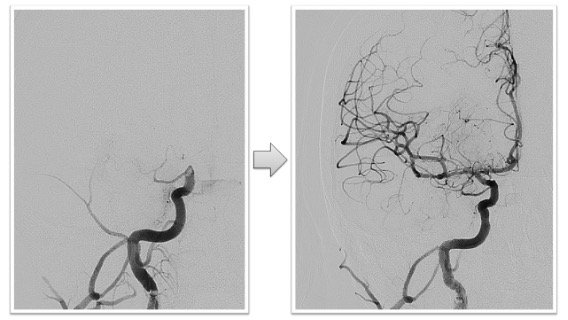

内頸動脈閉塞実例(*患者様の許可を得て掲載しています)

心原性脳塞栓症による左内頸動脈閉塞

右内頚動脈終末部の閉塞症例ですが、術後右内頚動脈から中大脳動脈、前大脳動脈などすべての末梢動脈への血流が回復しています。